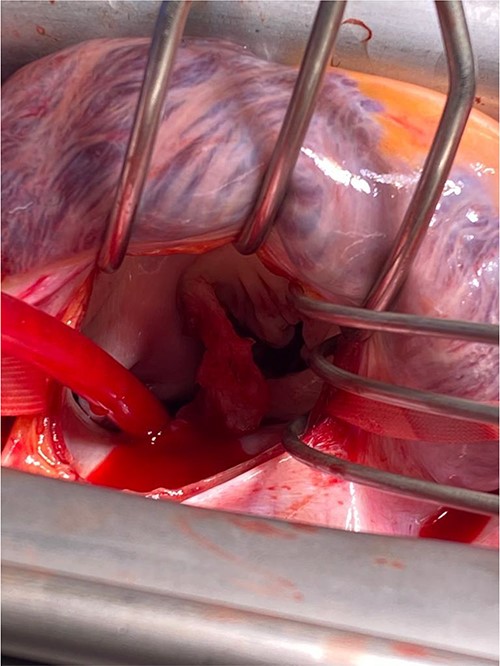

A CTPA was undertaken on Day 2, which excluded pulmonary embolism but confirmed bilateral peri-hilar consolidation and pleural effusions consistent with pneumonia. However, her pulmonary artery was dilated at 32 mm indicative of potential heart failure. On Day 5 of her ICU stay, a transthoracic echocardiogram was undertaken that revealed there to be severe mitral regurgitation including a mobile echogenic mass attached to the underside of the anterior mitral valve leaflet consistent with a vegetation (Figs 1 and 2).

Pre-operative TTE depicting mitral valve with vegetation (labelled).

Intra-operatively, femoral–femoral bypass was established and a 3 cm windsock vegetation was found with a 1.5 × 1.5 cm hole at the aortic inlet on the annular junction. The vegetation travelled from the LV to LA as shown in Figs 3 and 4. The vegetation was excised and the valve debrided, which resulted in moderate regurgitation from severe. Hence, a further 26 mm Physio II ring was placed resulting in no mitral regurgitation. The excised vegetation is shown in Fig. 5 and the post-op TTE images are shown in Figs 6 and 7.